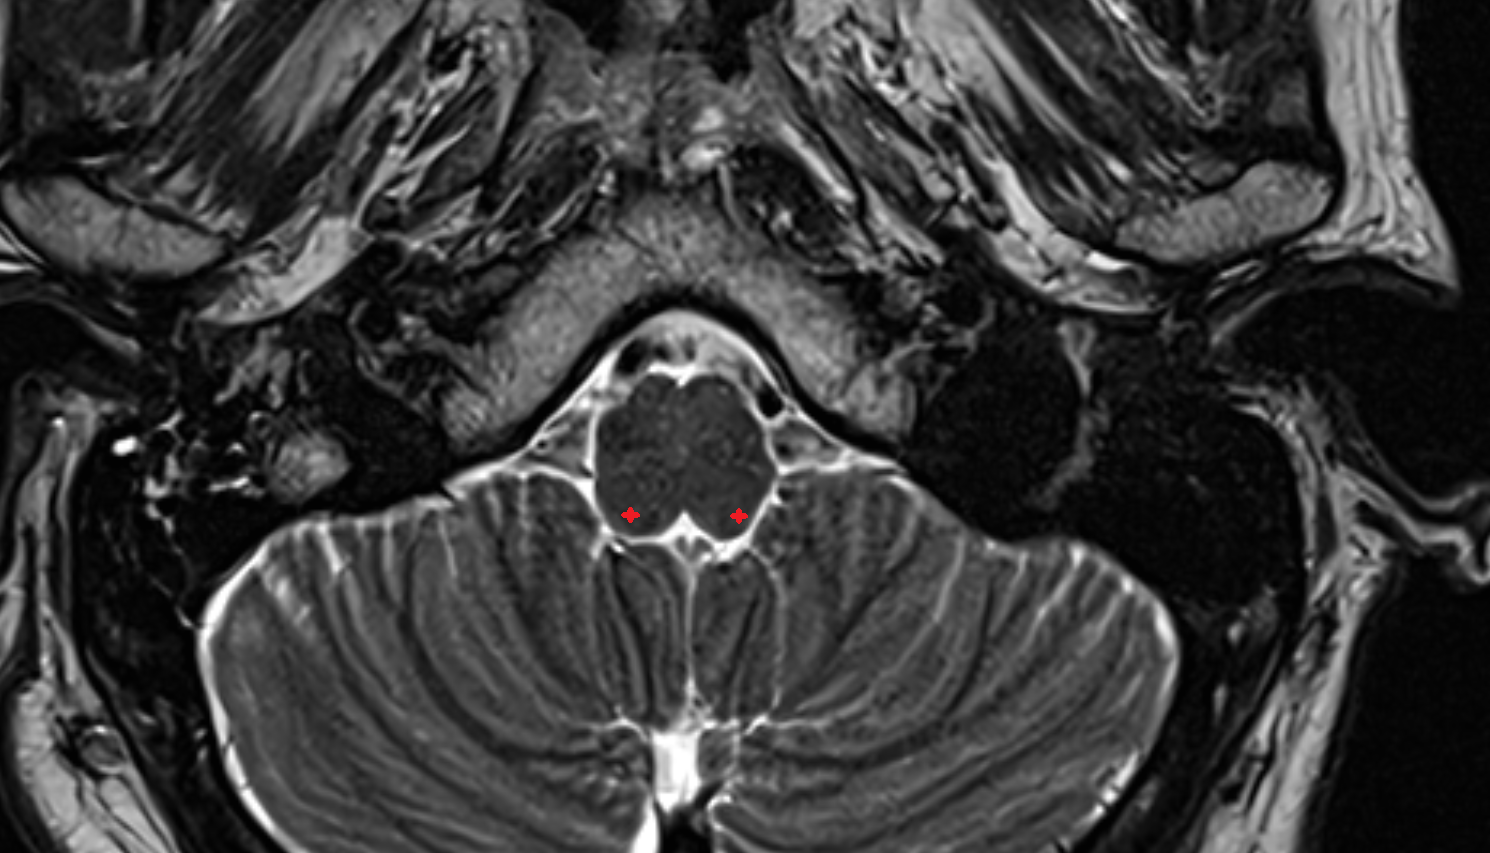

- Dentate nucleus

- Cornu Ammonis 1 (CA1)

- Cornu ammonis 2 (CA2)

- Cornu ammonis 3 (CA3)

- Cornu ammonis 4 (CA4)

- Cornu ammonis